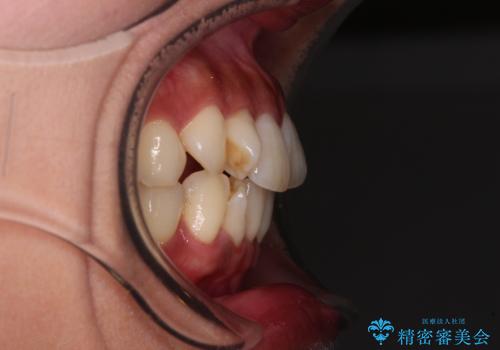

上顎最後臼歯は極端に外側を向いており、下顎骨に対して上顎骨が前方に位置していたため、補助装置により最後臼歯を一気に内側に引き込むとともに、上顎臼歯を後方移動させ、奥歯の咬み合わせが改善した後に、上下インビザラインにより歯列全体を整えていくこととしました。